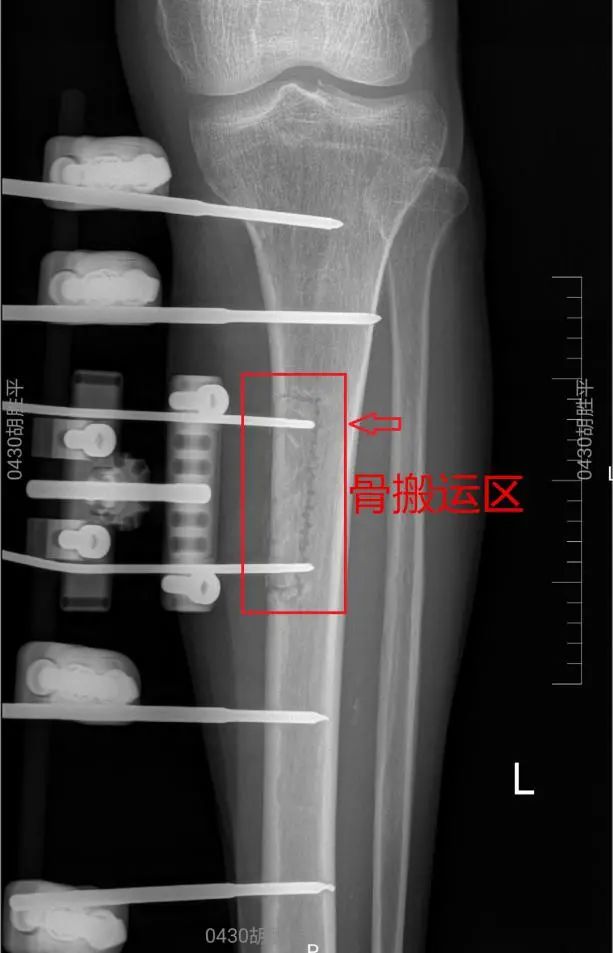

胫骨骨搬运区X线影像:

手术当天,副主任医师祖罡首先在患者左小腿前方做了一个大约10cm的小切口,显露小腿胫骨上段后,在直视下通过专用工具进行了人工“骨开窗”,对左腿术区骨开窗摘除后的骨块,使用了外固定支架固定;同时对右足部溃疡区进行了真空封闭引流术。

而这场手术只是倪大爷恢复的第一步。回到病房后,患者只需在祖医师的指导下对支架的螺栓进行转动,就可以实现对左小腿胫骨骨块的提拉横向搬运。骨块的横向搬运能够促进患者双下肢血管、神经的自我再生修复,同时,因为避开了右脚的创口,降低了感染风险,最终了实现糖尿病足坏死感染组织的自我修复。